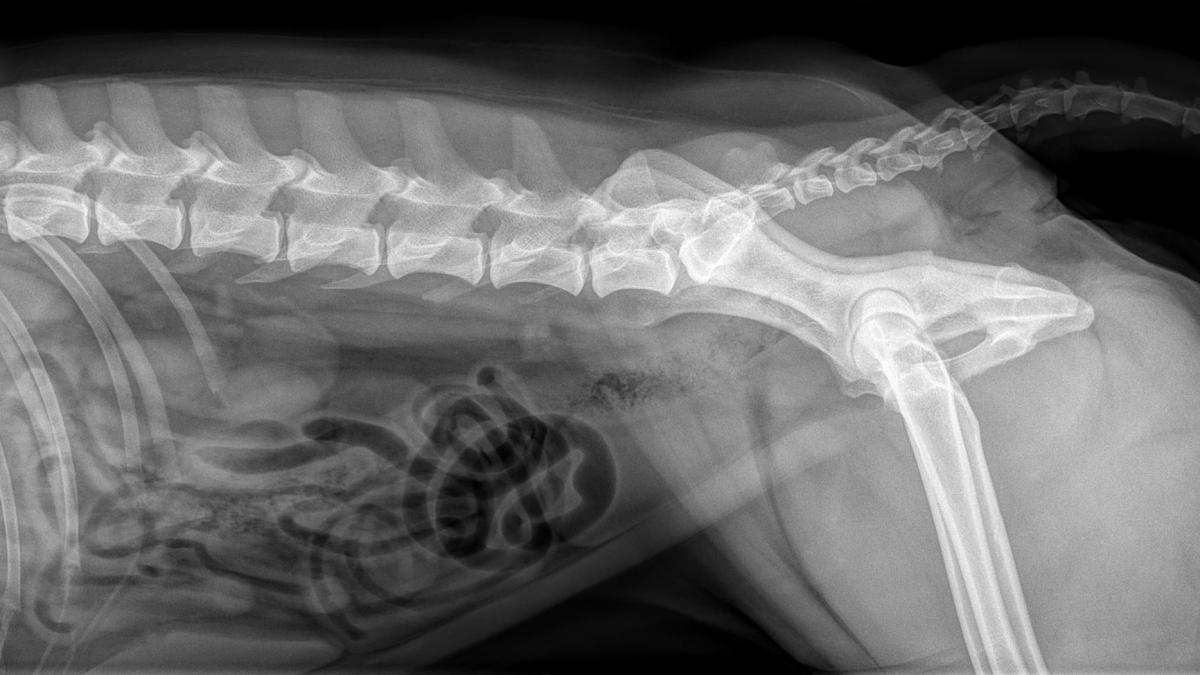

Eine leistungsstarke Röntgenanlage, ein modernes High-End-Ultraschallsystem und ein Videoendoskop ermöglichen uns ein breites Spektrum an bildgebender Diagnostik.